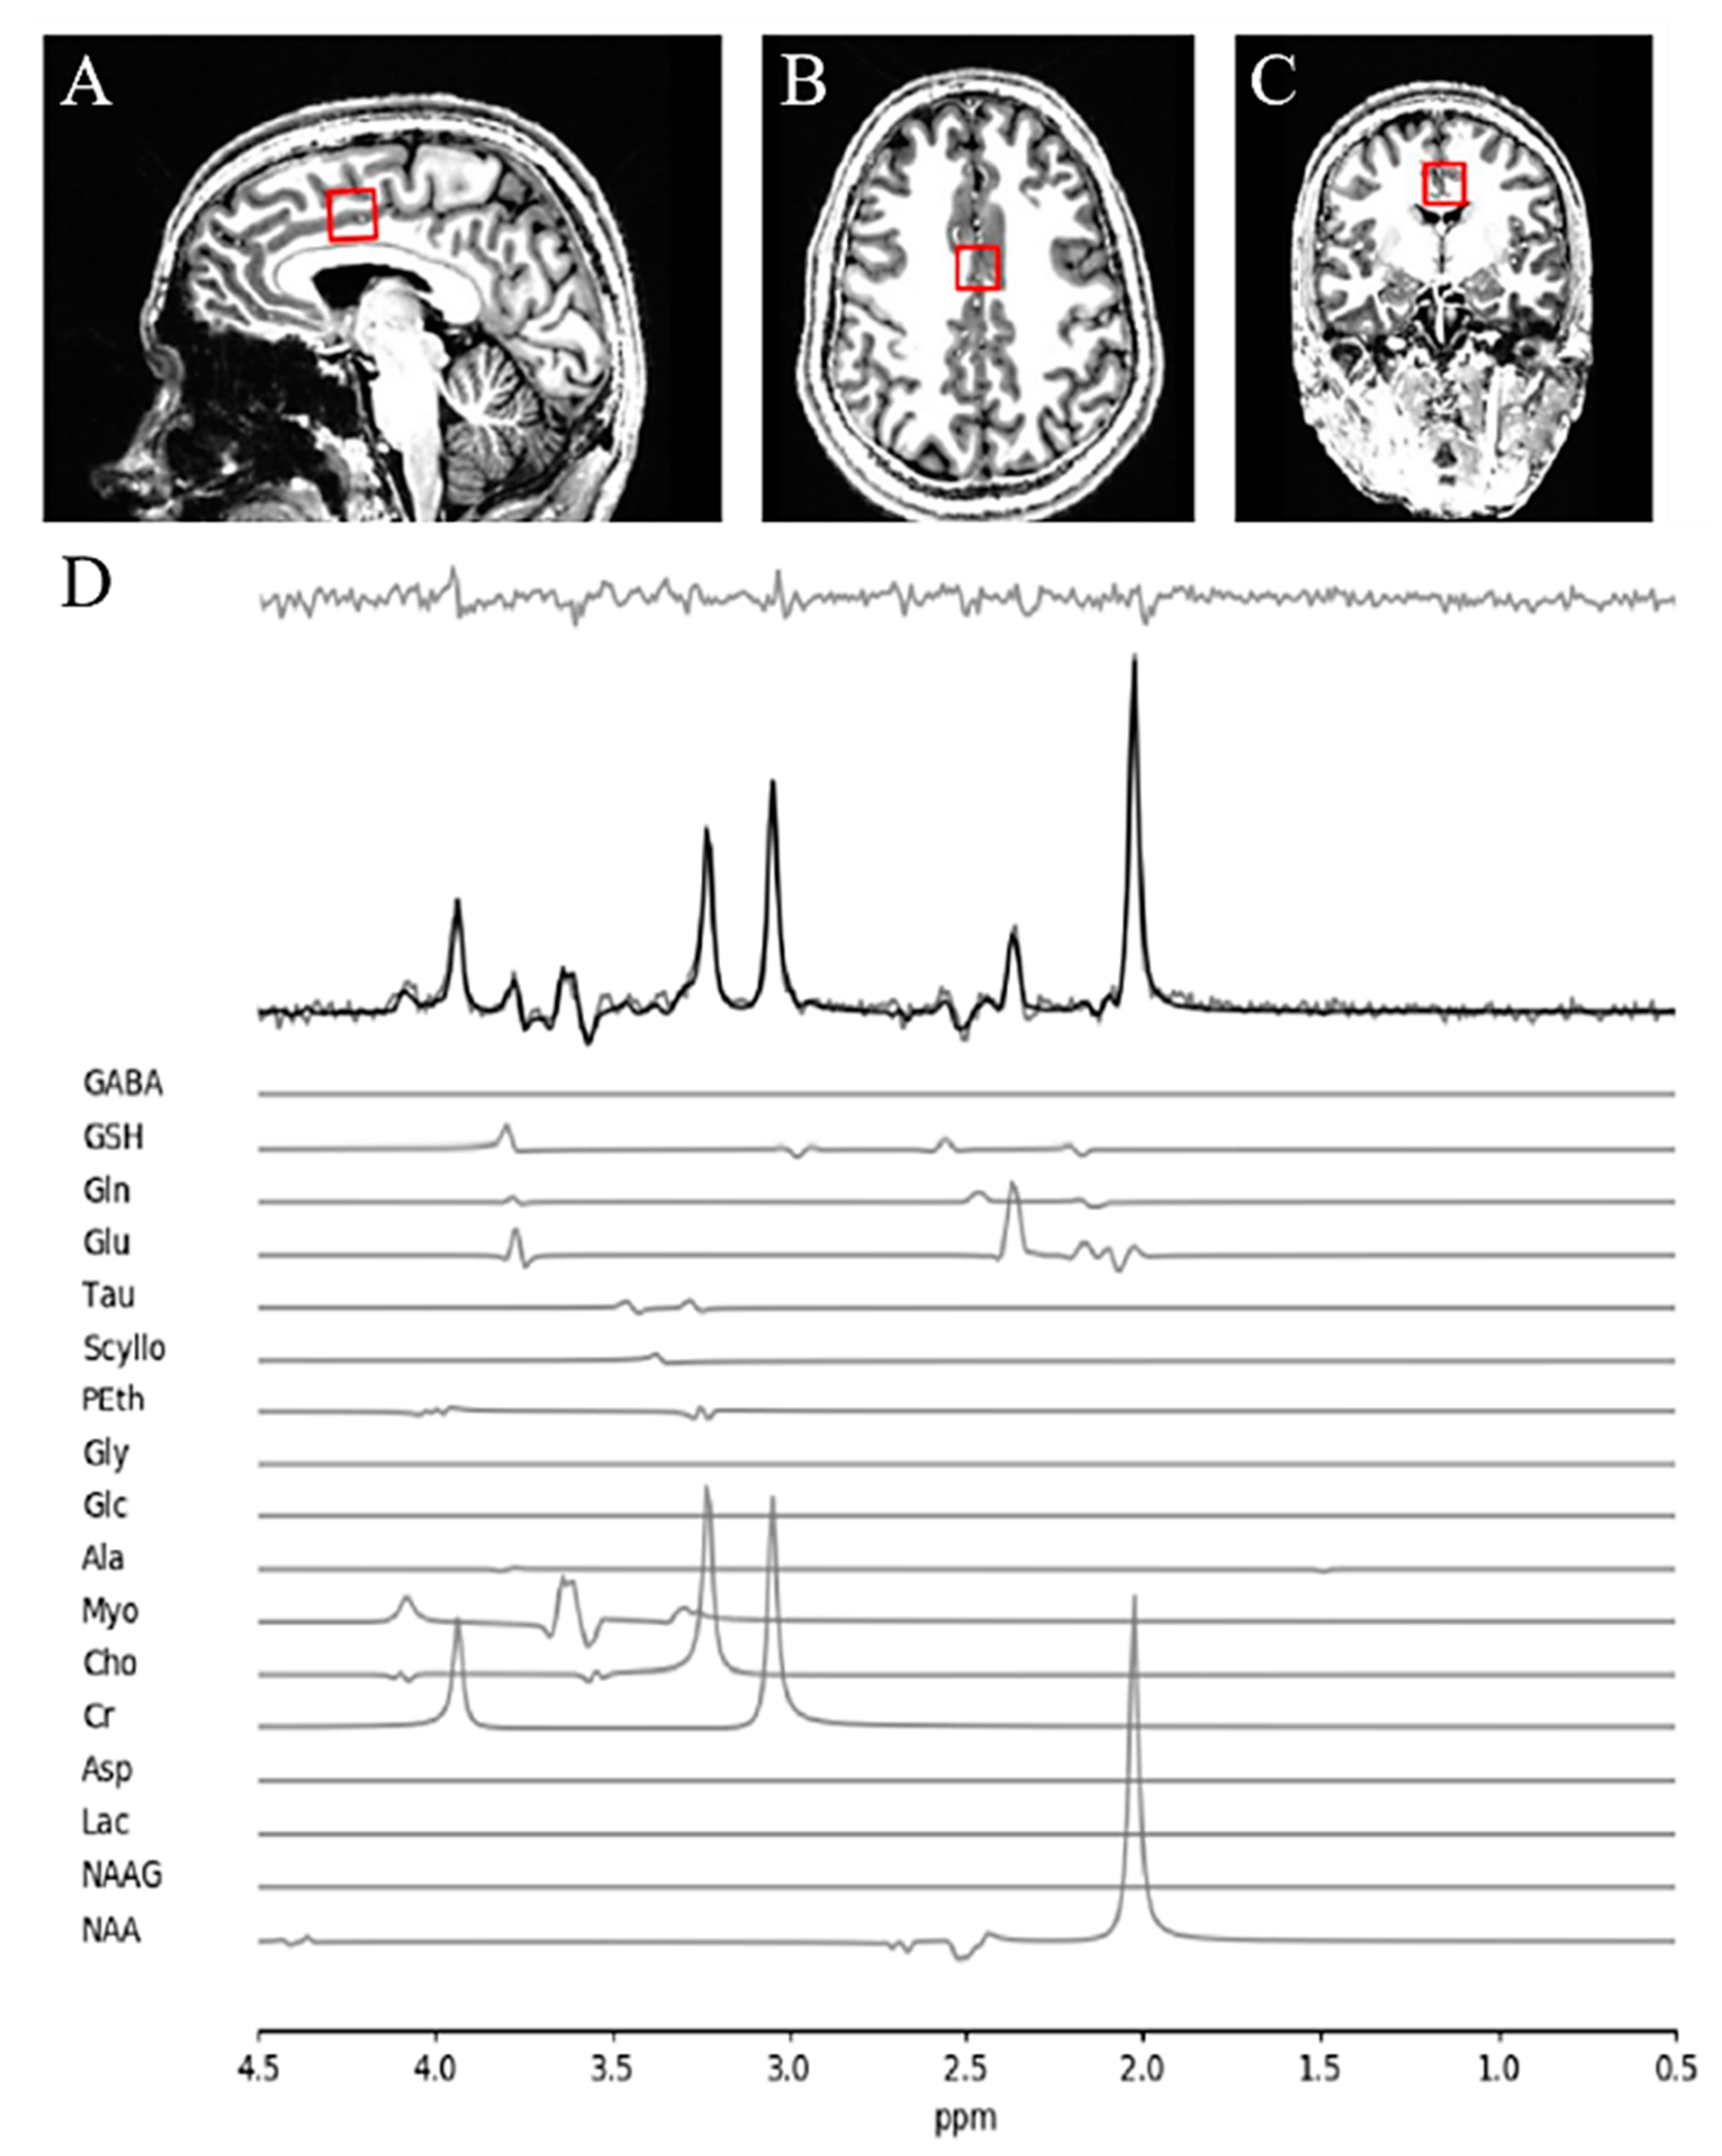

All data was acquired using a 680-mm neuro-optimized 7 T MRI scanner (Siemens MAGNETOM Plus, Erlangen, Germany) equipped with an AC84 II head gradient coil and an 8-channel Tx, 32-channel Rx radiofrequency coil. We defined a 2.0 × 2.0 × 2.0 cm (8 cm3) 1H-MRS voxel on the bilateral dACC (Figure 1). To this aim, we used a two-dimensional sagittal anatomical image (37 slices, TR = 8000 ms, TE = 70 ms, flip-angle (α) = 120°, thickness = 3.5 mm, field of view = 240 × 191 mm) as reference. We defined the voxel position both by setting the posterior face of the voxel in coincidence with the precentral gyrus and by setting the position of the inferior face of the voxel to the most caudal point not part of the corpus callosum. We set the voxel angle tangentially to the corpus callosum. A semi-LASER 1H-MRS sequence (TR = 7500 ms, TE = 100 ms, bandwidth = 6000 Hz, Navg = 2048) was used to acquire 32 channel-combined, [18] VAPOR water-suppressed spectra as well as a water-unsuppressed spectrum (Navg = 1) to be used for spectral editing and quantification. We asked all participants to fix their gaze on a white cross (50% gray background) during MRS acquisition. All scanning took place at the Centre for Functional and Metabolic Mapping of Western University, London, Ontario.

The quality of metabolite quantification was measured using CRLB percentages for both groups using a CRLB threshold 30% for glutathione to determine inclusion toward further analyses, in line with our prior study [24]. There was no significant difference in CRLB between the FES patients and HC subjects for both metabolites being reported in this study. A sample of fitted spectrum for a single participant is presented in Figure 1.

Figure 1. MRS voxel and spectra. (A) Sagittal, (B) axial, and (C) coronal view of voxel positioning on the dorsal anterior cingulate cortex (dACC). (D) Sample spectra obtained from a single healthy participant. The bold black line represents the fitted spectra with the residuals above (the gray line above the fitted curve) and each individual metabolite contribution below.